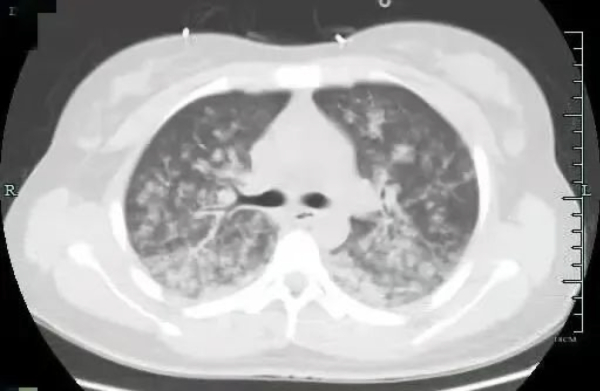

小月肺部检查发现已是“白茫茫一片”。

“患者送来时已经昏迷状态,严重胸闷气促,血氧饱和度低于90%。”急诊医生表示,根据肺动脉CTA、肺部CT等检查结果显示,小月为肺脂肪栓塞,“肺部已是白茫茫一片,产生严重的炎症因子风暴”。